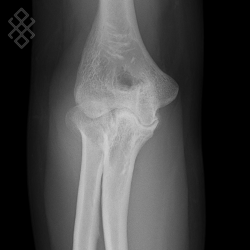

Radiographie du Coude

Positionnement

Vous serez installés en position debout avec le bras posé sur la table d'examen.